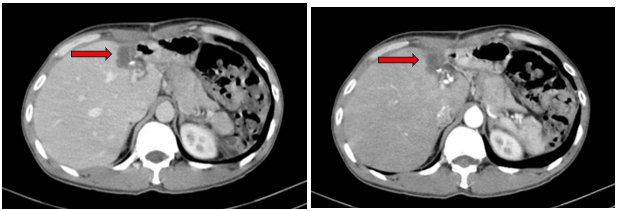

- Chụp cắt lớp vi tính ổ bụng:

Hình 1: Trên hình ảnh CT ổ bụng cho thấy nhu mô gan trái có khối lớn, kích thước khoảng 92x70mm, tỉ trọng hỗn hợp trước tiêm, sau tiêm ngấm thuốc không đồng nhất, có phần ngấm thuốc mạnh thì động mạch, thải thuốc thì tĩnh mạch và thì muộn, tăng sinh mạch trong khối. Khối đẩy lồi bao gan, không thấy thâm nhiễm xung quanh hay hay to lân cận, theo dõi HCC

(ung thư biểu mô tế bào gan) (mũi tên đỏ)